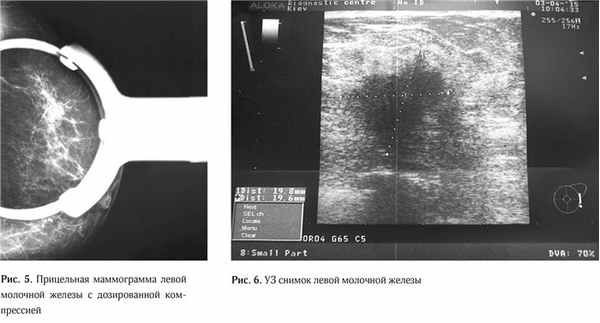

В виду того, что данные маммографии в стандартных проекциях были малоинформативные, была выполнена прицельная маммограмма левой молочной железы с дозированной компрессией, что позволило более чет ко визуализировать участок нарушения архитектоники ткани, оценить его размеры и точную локализацию (Рис. 5).

По данным ультразвукового исследования молочных желез (03.04.15 г.): в левой молочной железе по передней аксиллярной линии в проекции 7 межреберья визуализируется очаговое образование сниженной эхогенности, неоднородной структуры, без четких контуров, с признаками инфильтративного роста, с вертикальной ориентацией максимальной оси размерами 19,8х20,0 мм. Кровоток интранодулярный, визуализируется единичный питающий сосуд (Ri (resistive index) – 0,63). Пре- и ретромаммарное пространства не изменены. Заключение: УЗ-признаки рака левой молочной железы. (Рис. 6).